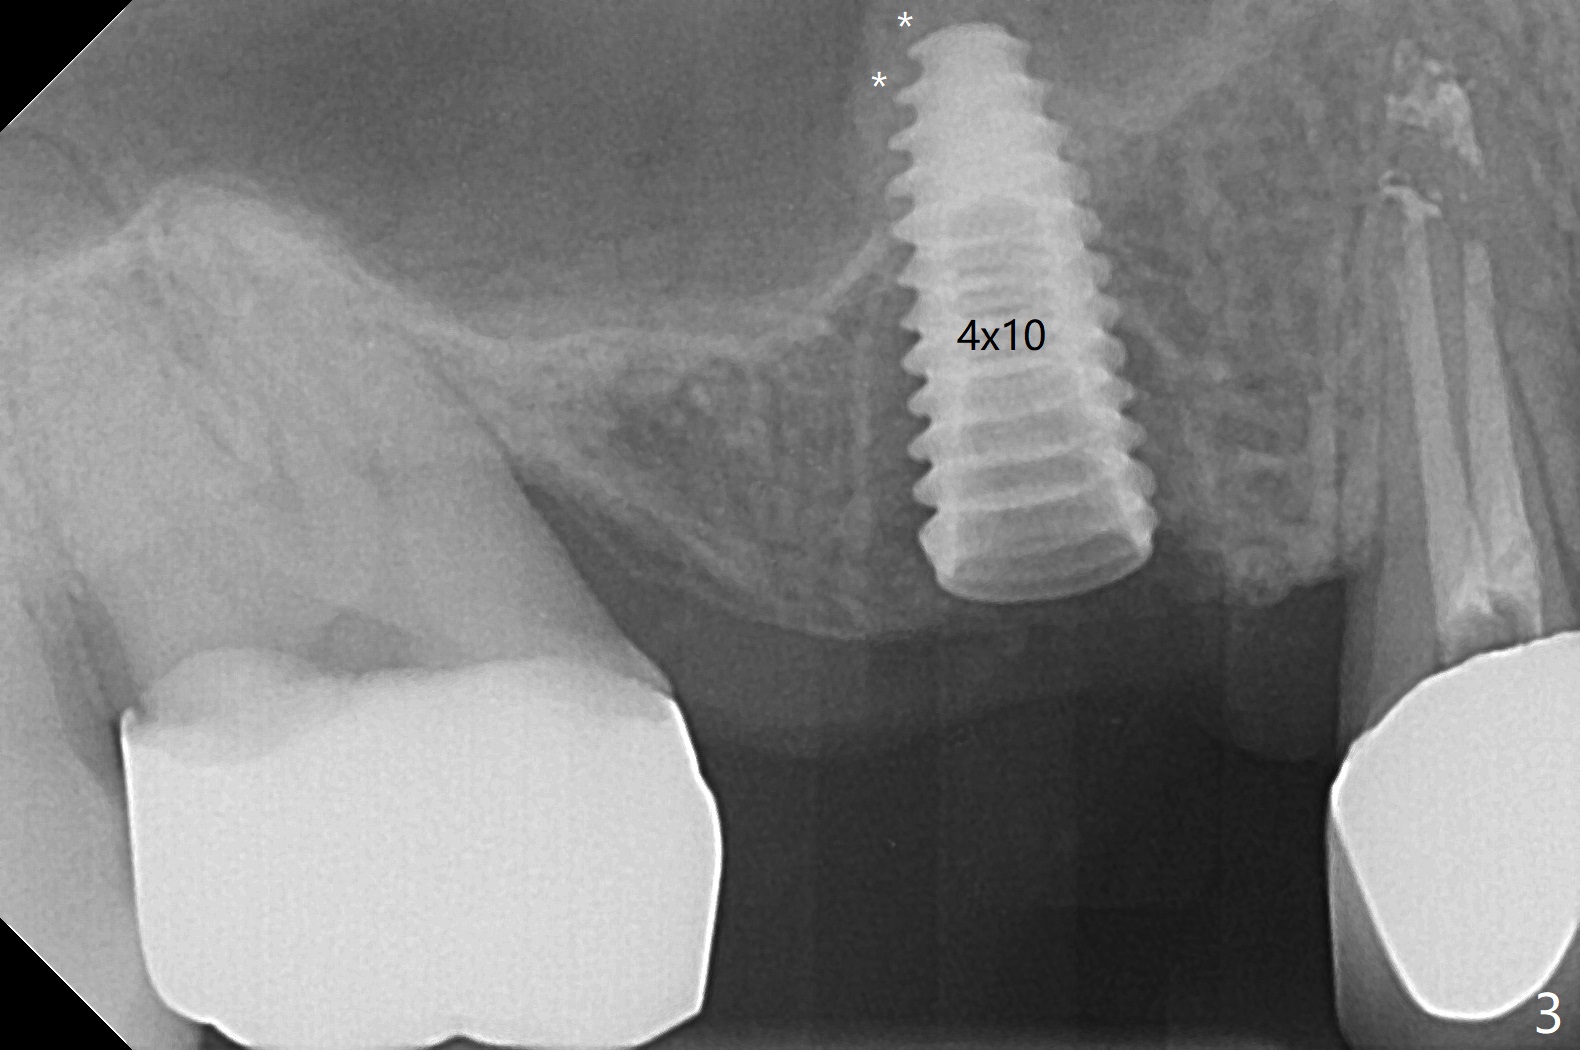

After flattening the root stump with surgical burs and bone trimmer at #4 (Fig.1), it is difficult to use point drill and 2.2x7.3 mm drill because of incomplete engagement of drill cylinder with guide sleeve (Fig.2). The initial osteotomy seems to be buccal. With removal of the remaining root, it is much easier to finish osteotomy (better engagement of drill cylinder with the sleeve) and sinus lift with dummy implants (Fig.3,4 (*: bone graft)). Finally a 4.5x10 mm implant is placed (basically in the middle of the socket with even buccal and palatal gaps) with primary stability and a cemented abutment is hand tightened (after 5.5 mm profile drill) for an immediate provisional (Fig.5). The gingiva is healthy around the provisional with almost perfect seal 2 weeks postop (Fig.6 P). There is no obvious bone loss 7 months postop (Fig.7). There is apparent mature bone in the sinus 9 months postop (Fig.8 *).